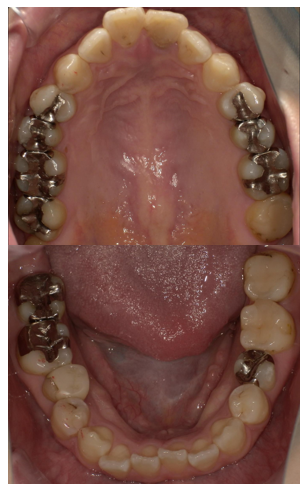

症例1

治療前

治療後

| 主訴 | 前歯見た目気になる。 |

| 診断 |

歯の変色、左上2口蓋側転位 |

| 治療内容 | 左上12再根管治療、左上12審美ジルコニアクラウンによる補綴治療 |

| 年齢・性別 |

25歳、女性 |

| 治療期間 |

2ヶ月 |

| 治療費用 | 220,000円 |

| リスク・副作用 | 歯の切削 |